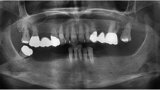

Fig. 1: Panoramic radiograph of the initial dental status.